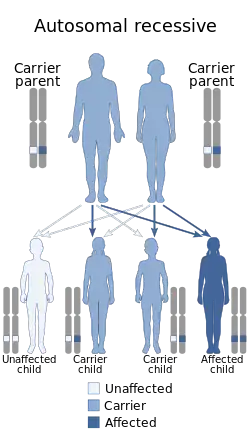

| Pontocerebellar hypoplasia is inherited in an autosomal recessive manner | |

Pontocerebellar hypoplasia (PCH) is a heterogeneous group of rare neurodegenerative disorders caused by genetic mutations and characterised by progressive atrophy of various parts of the brain such as the cerebellum or brainstem (particularly the pons).[1] Where known, these disorders are inherited in an autosomal recessive fashion. There is no known cure for PCH.[2]

The mutated genes in PCH are autosomal recessive, which means that parents of an affected child each carry only one copy of the damaged gene. In each parent the other copy performs its proper function and they display no signs of PCH. A child inheriting two damaged copies of the gene will be affected by PCH.[2]